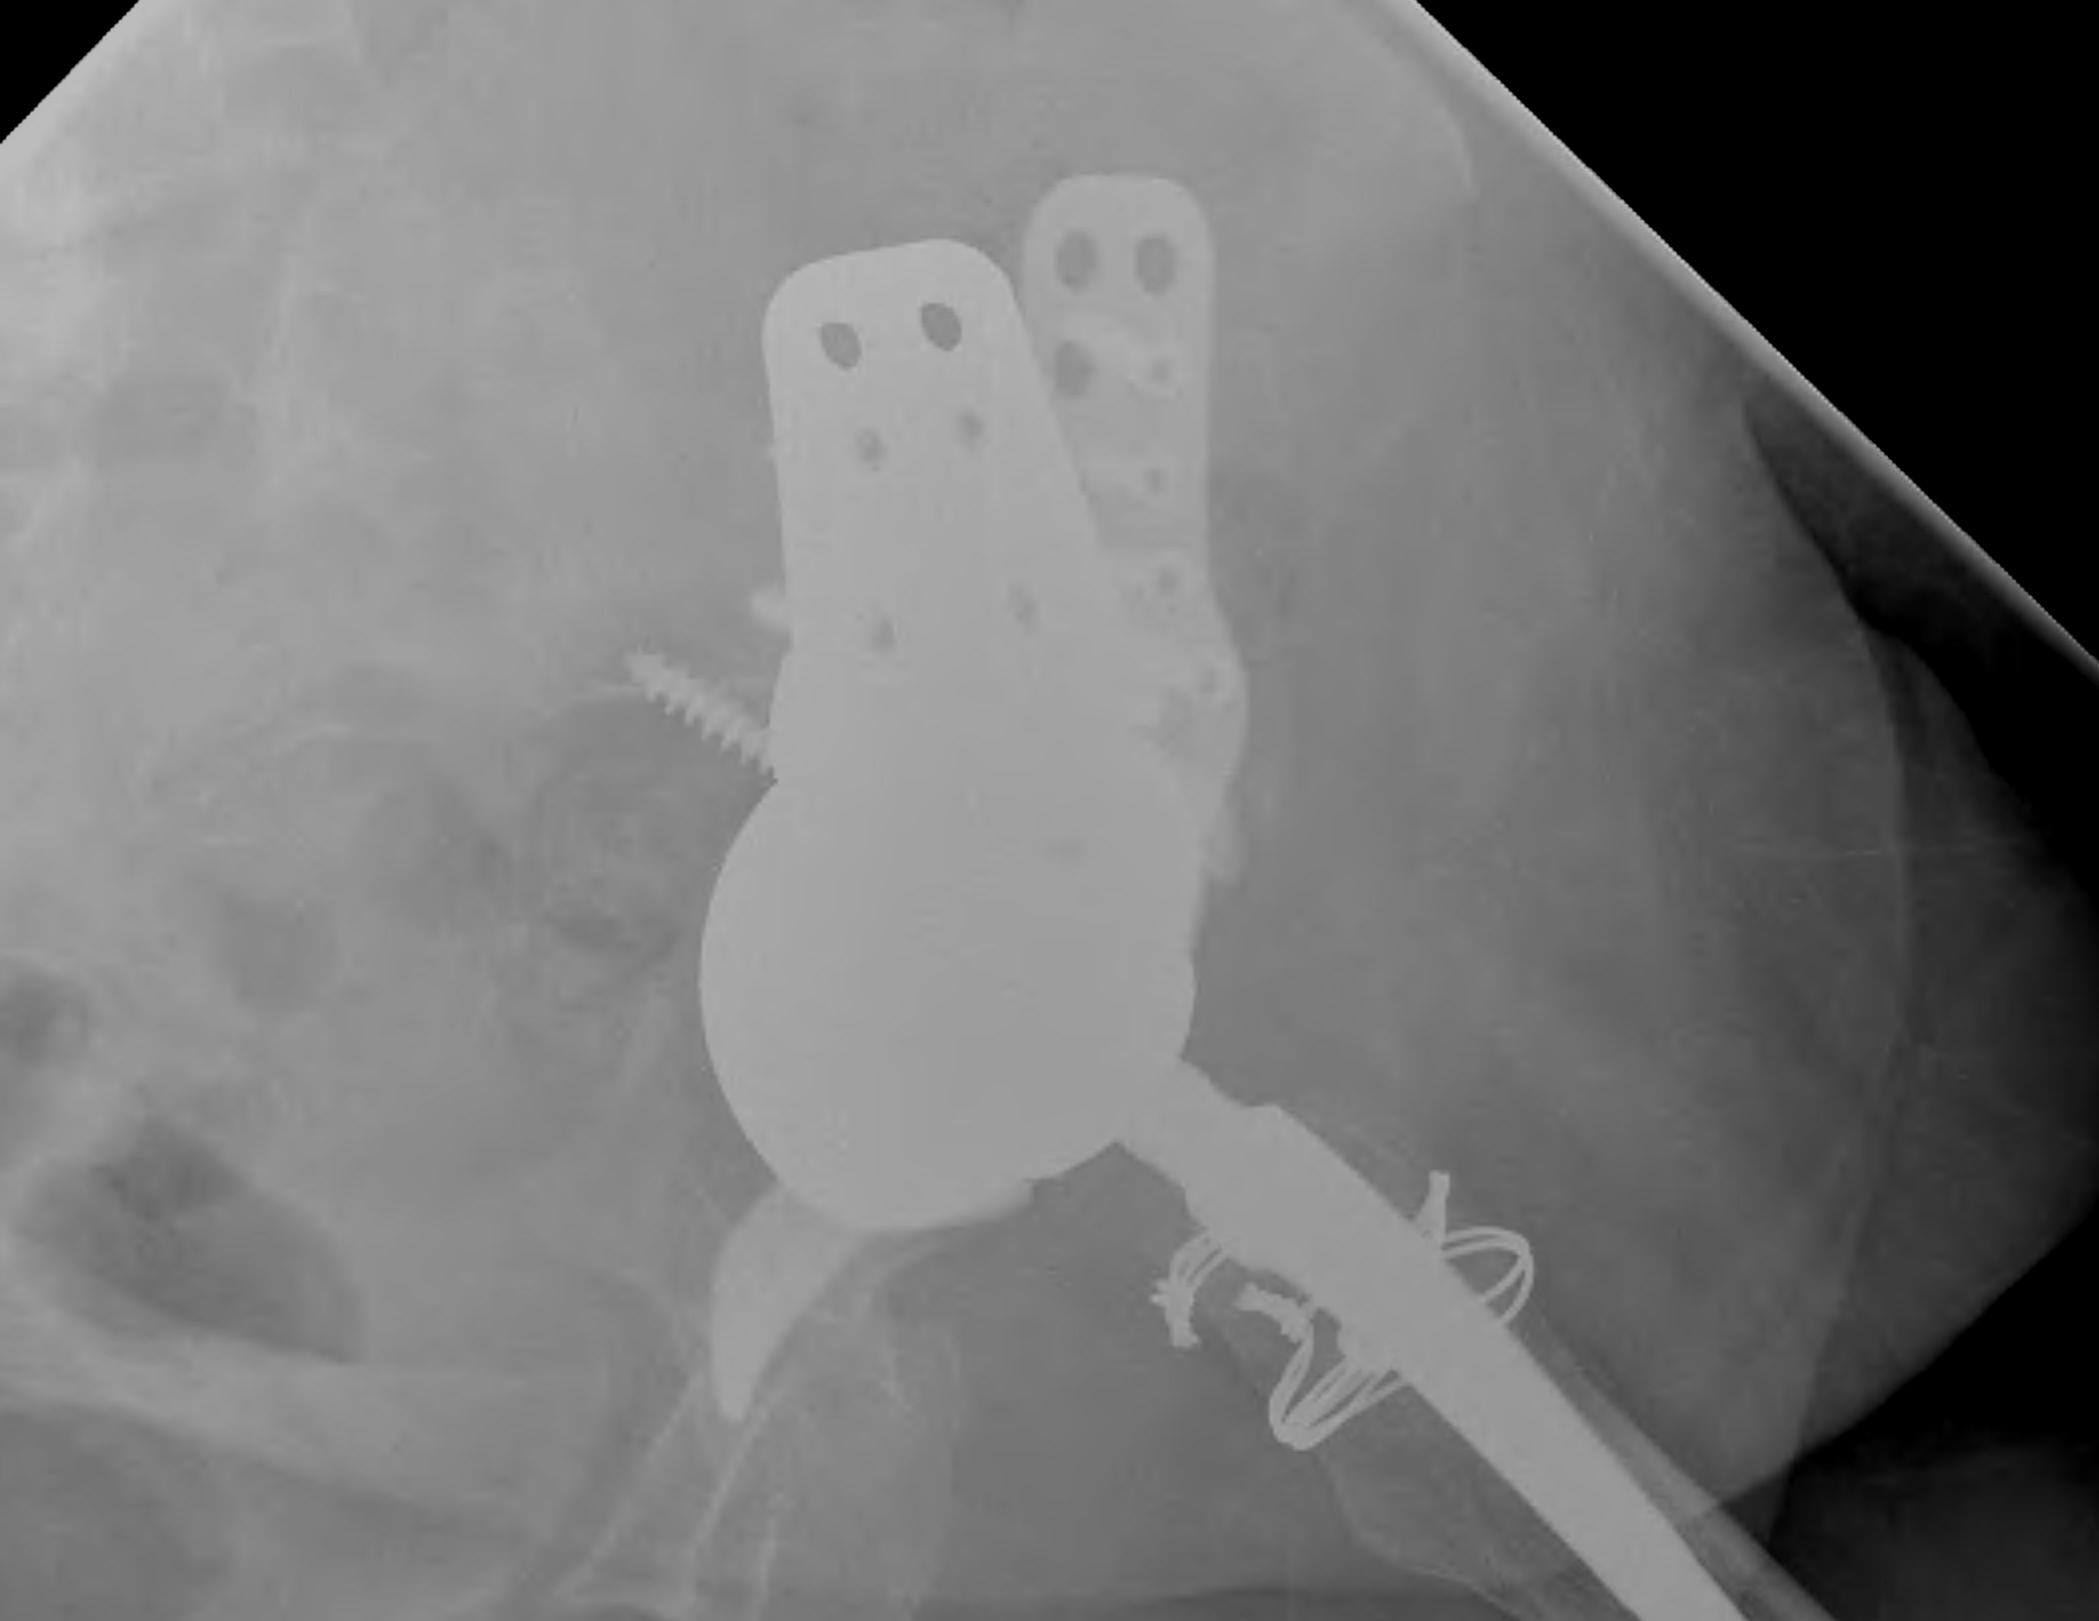

Option: Custom-made triflange components

CT guided model of pelvis

- custom made acetabular cage

- fits defect exactly

- flanges perfectly designed and not malleable to improve strength

- HA coated

- cement poly cup into it

Indications

- massive defects

Results

- 90% 4.5 year survival in complicated patients